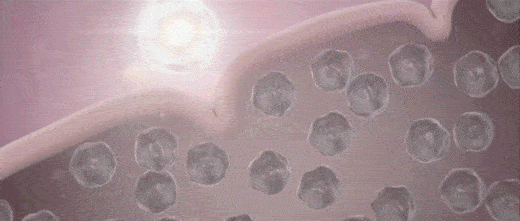

外泌体(Exosome)是由细胞分泌的30-150nm的微小膜泡,携带蛋白质、mRNA、miRNA、生长因子等多种生物活性物质。

透射电镜下的外泌体